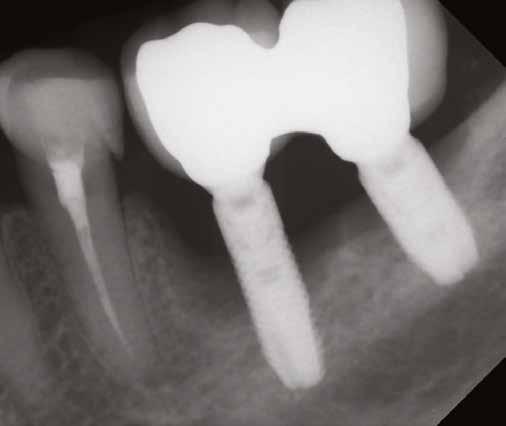

1. ábra: Dr. Jung 10 éves kontrollal rendelkező 4.7-es helyén levő Dentium short implantációja. Preoperativ CT, ínyformázó 4 hónappal a műtét után, valamint 4 hónap múlva 4.7-es szólókorona.

2. ábra: Dr. Park esete. 4.6-os fogon levő jelentős csontfelritkulás röntgenképe, extractio és iGBR alkalmazása Osteon Xenoval. 4 hónap múlva Dentium short implantátum, majd 4 hónap múlva korona készítése.

Prof. Jung Ui Won szöuli parodontológus a rövid implantátumok rizikómenedzselésével foglalkozott előadásában. Eseteket mutatott be 10 éves követéssel, ahol rendkívül alacsony csontkínálat mellett tudott sikeresen short megoldást találni.

Dr. Park Jung Chul, a szöuli Katolikus Egyetem előadója a páciens és orvos-barát megoldásként alkalmazott, nyitott gyógyulású iGBR technikával foglalkozott. Egyik esetében a jobb alsó 6-os fogon periapicalis léziót mutatott be, majd extractio, iGBR alkalmazása, és 4 hónappal később implantáció, továbbá korona készítése történt.